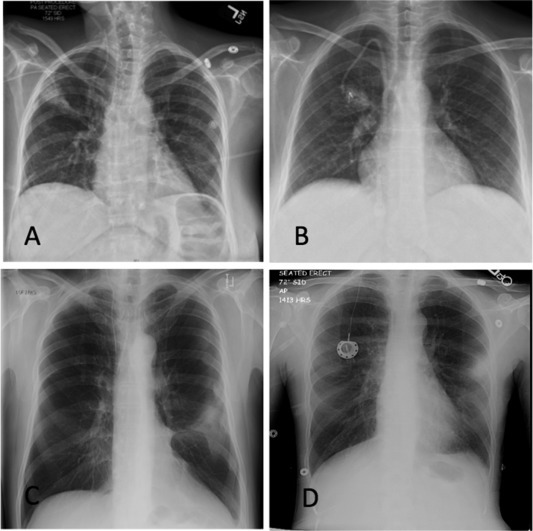

Panel B. A Gram stain of the patient's sputum shows macrophages and polymorphonuclear leukocytes but no L. pneumophila (top picture), whereas a silver stain shows the organisms (arrows) and is the preferred sputum stain (bottom picture).

Panel C. Four chest x-rays of patients with early stage LD.